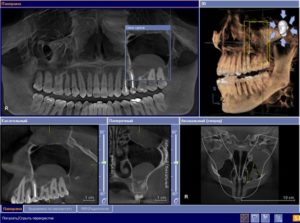

СПРАВКА! Доктор при пальпации больной зоны обнаруживает характерный для кисты звук, напоминающий «хруст пергамента». Новообразование на рентген-снимке выглядит как темное круглое пятно. Для уточнения диагноза используют метод конусно-лучевой томографии — отображение патологического очага в 3 полостях.

Первоначально специалист проводит опрос больного и выясняет жалобы. Врач обращает внимание на наличие кариеса, пломб и имплантантов. С помощью рентгенограммы оценивается состояние носовых пазух. Скрытые патологии исследуются благодаря ортопантомограмме. Снимок челюсти с зубами позволяет увидеть характерные признаки болезни.

Компьютерная томография помогает обнаружить причину, вызывающую резорбцию кости. Данный метод исследования наиболее качественный, т. к. он позволяет различать мягкие ткани и кости.

С помощью томографии врач может определить точную причину затянувшегося синусита.